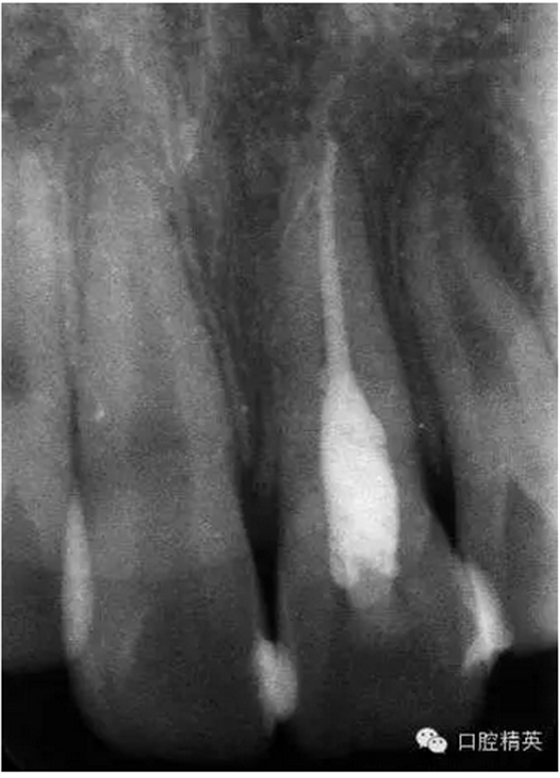

x線檢查:21牙槽窩空虛,窩內(nèi)未見其他遺留物。

圖3.患者21根尖片,牙槽窩空虛,無變形。